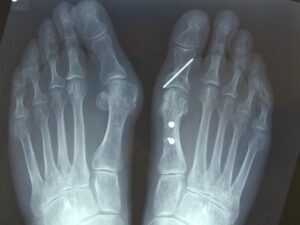

When do screws, wires or plates need to be removed? These are used in your operation to hold the cut pieces of bone together. The fixation screws/wires etc rarely cause problems and are perfectly safe if left in the body.

The screws serve a purpose while the bone is healing; after that they become redundant. Sometimes, they can get pushed out of the bone and cause discomfort to surrounding soft tissues or be felt beneath the skin and lead to footwear irritation. If this is the case, they require removal.

Very rarely, the metal in the screws or wires can cause tissue sensitivity.